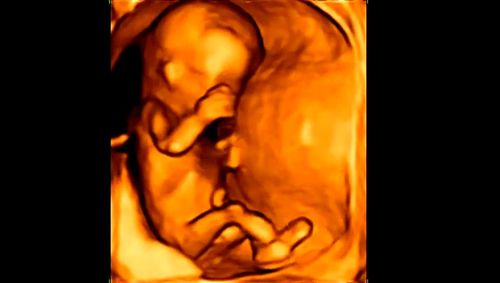

四维彩超男女区别,四维彩超男女区别照片

四维彩超出图,怎么看男女?

四维彩超男女区别照片

四维彩超图片男女

四维彩超图片